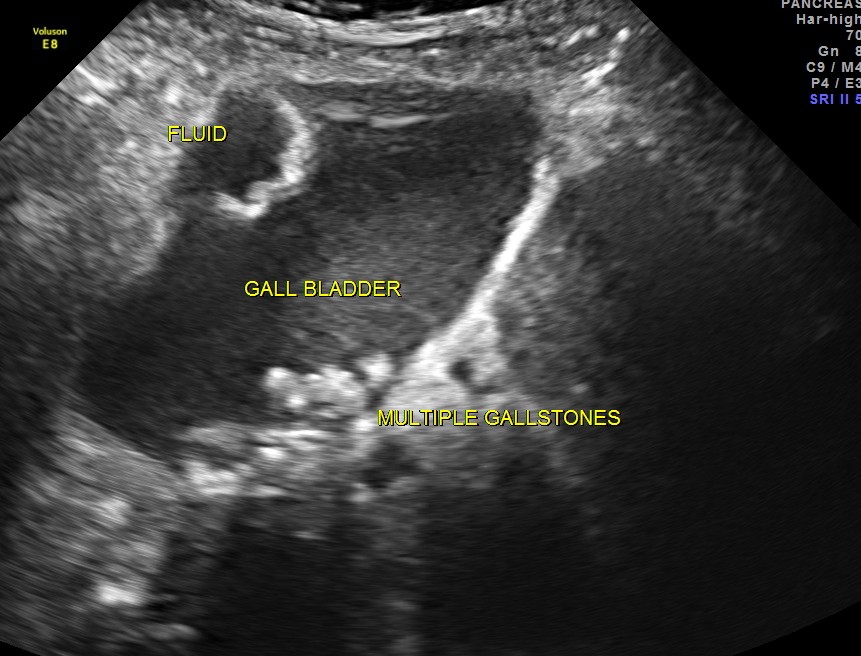

Her ultrasound showed the following findings :

grossly distended gallbladder , with sludge and gallstones and fluid around the gall bladder.

The diagnosis was : acute calculous cholecystitis , cystic duct stones causing a rupture and fluid collection around the GB and loculated sub diaphragmatic collection with reactive mild right pleural effusion . Endometrial fluid collection needed further evaluation.